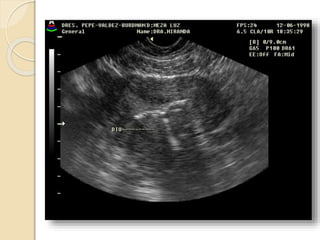

Quistes Endometrósicos:

Clínicamente se manifiesta por dismenorrea,

dispareunia e infertilidad.

La lesion mas detectable por la imágenes esta

constituida por los quistes endometrosicós

(endometriomas) que se forman a partir de los

implantes ováricos configurando los quistes

“achocolatados”.

Se observan quistes de paredes relativamente

gruesas e irregulares con débiles ecos en su

interior debido al contenido hemático.